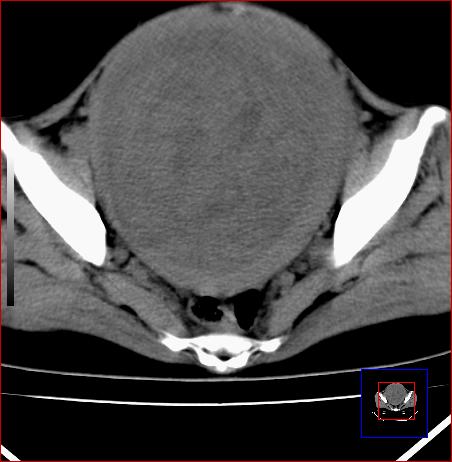

标题: CT15141:子宫肌瘤还是卵巢肿瘤 [打印本页]

标题: CT15141:子宫肌瘤还是卵巢肿瘤

腹部包块1年余,近两月明显增大,月经量多

病灶呈实性包块,边界清晰,似与子宫分界不清,考虑:子宫肌瘤

子宫体积增大,内密度不均匀。边缘清晰。考虑子宫肌瘤。